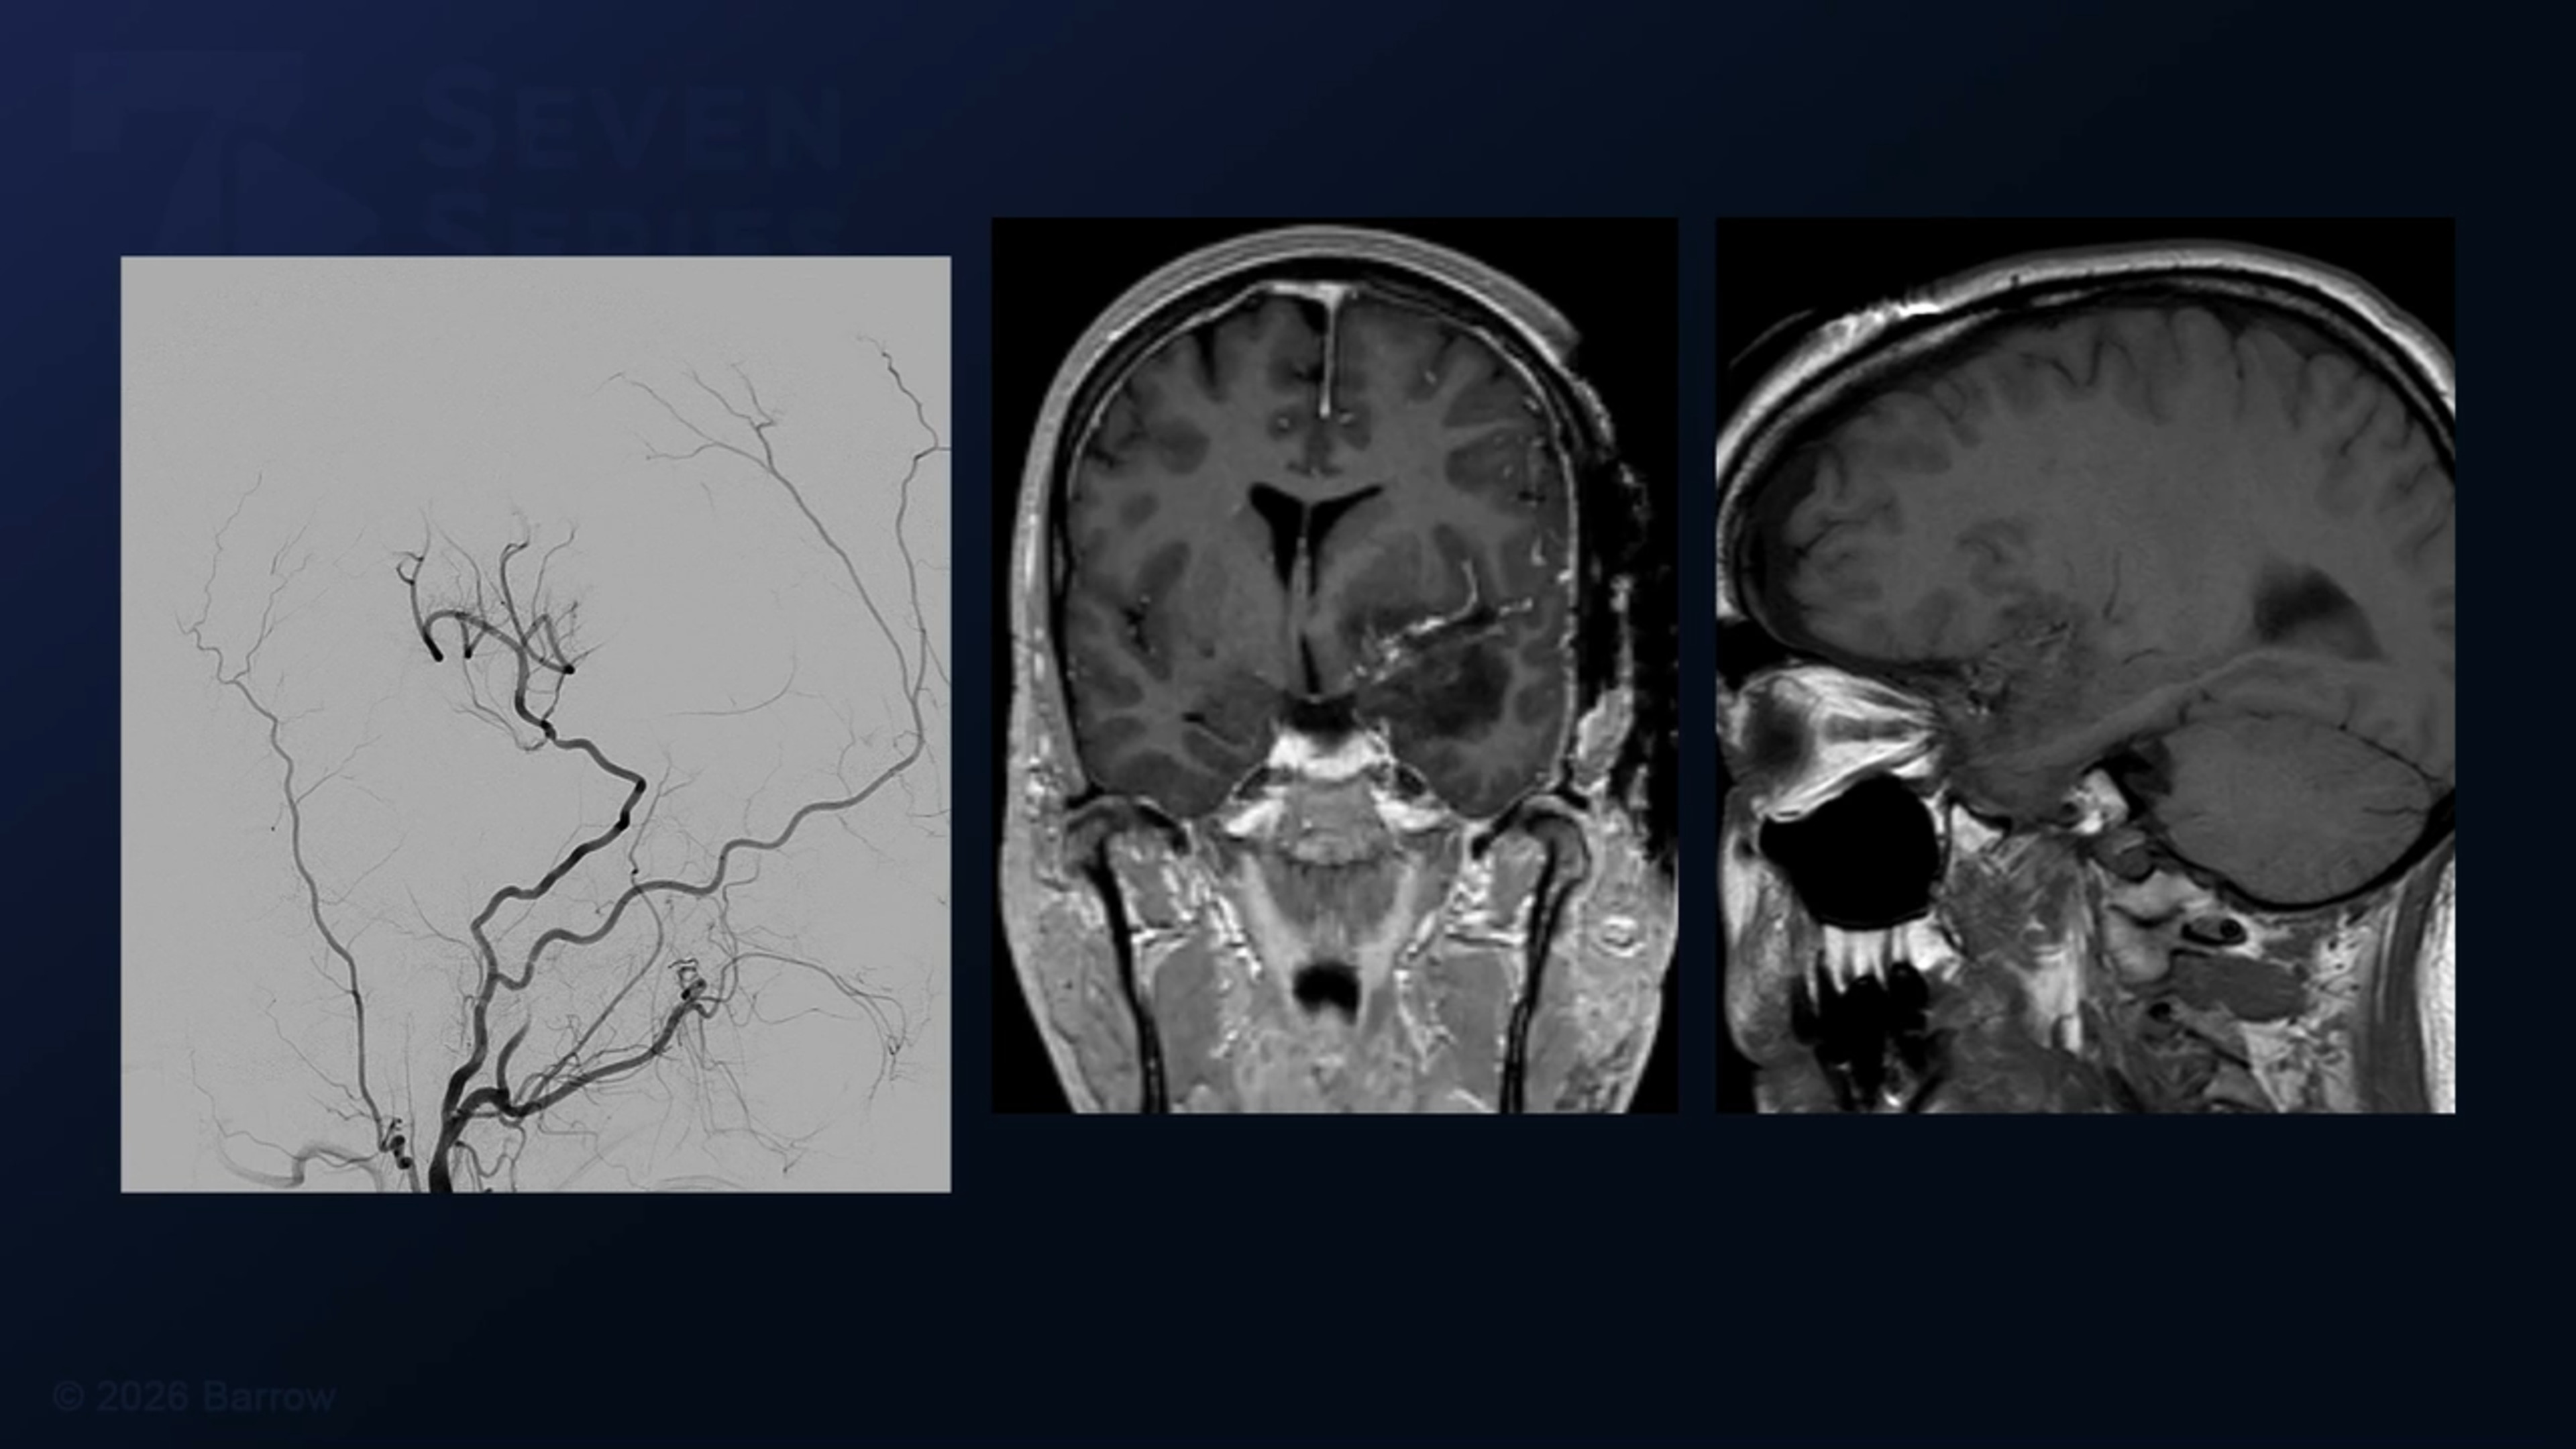

#501: Pterional Craniotomy and Extradural Anterior Clinoidectomy for Resection of a Clinoidal Meningioma with STA-MCA Bypass

Episode 501 of Seven Series shows a pterional craniotomy and extradural anterior clinoidectomy for resection of a clinoidal meningioma with STA-MCA bypass.